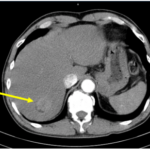

Case lâm sàng: Điều trị miễn dịch kết hợp thuốc kháng tăng sinh mạch cho bệnh nhân ung thư biểu mô tế bào gan tại trung tâm y học hạt nhân và ung bướu – BV Bạch Mai

Case lâm sàng: Điều trị miễn dịch kết hợp thuốc kháng tăng sinh mạch cho bệnh nhân ung thư biểu...

Ca lâm sàng: Điều trị thành công bệnh nhân ung thư tuyến giáp đã di căn xương cột sống sau 16 năm tại Trung tâm Y học hạt nhân và Ung bướu

GS.TS. Mai Trọng Khoa, PGS.TS. Phạm Cẩm Phương, Ths Lê Quang Hiển, BS. Vũ Thị Huyền Trung tâm Y học hạt...